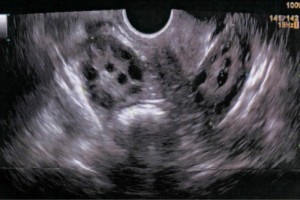

Diplomados en Ultrasonografía